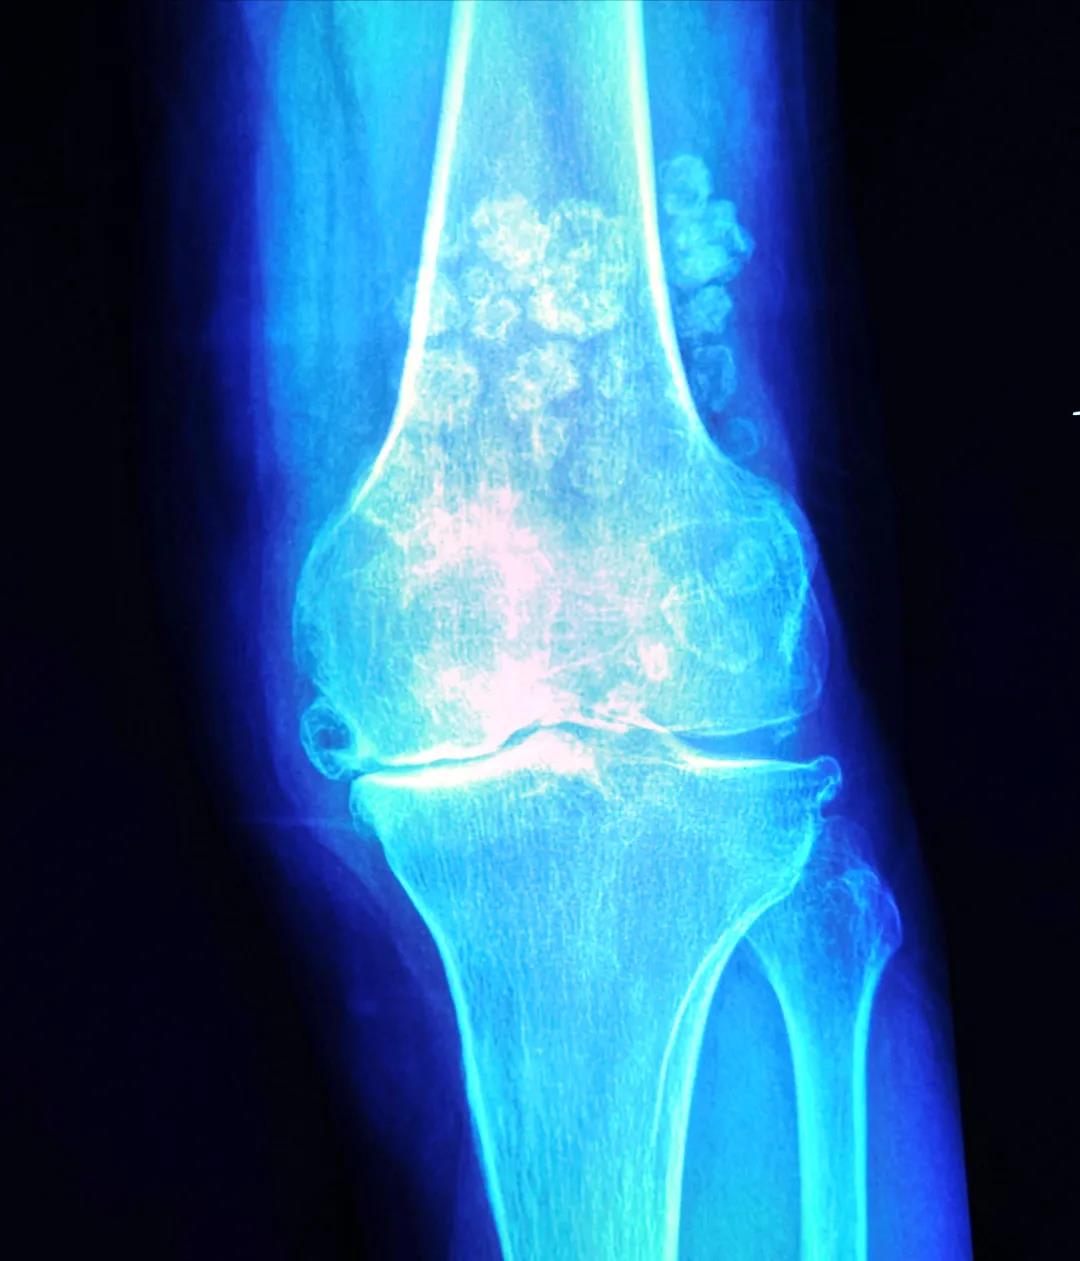

来自青海农村的68岁的李婆婆,由于长年累月的繁重农活,饱受双膝疼痛15年,从40多岁就不能利索地行走了。近3年病情加重无法行走,一度卧床休息几个月。到当地各地医院求诊,均因严重的“滑膜软骨瘤病”,医生都难以为其手术治疗。后经多方打听,家人得知新桥医院骨科擅长治疗此类疾病,并且还能通过微创精准的方式完成膝关节置换手术,所以不远千里前往重庆就诊。

张瑗副教授在接诊李婆婆后,经过详细的术前检查,判断能通过人工膝关节置换为其解除病痛,且能借助最新的机器人辅助外科手术系统,进一步提高膝关节置换的手术精准度,随即决定邀请这位“新人”为李婆婆一同手术。